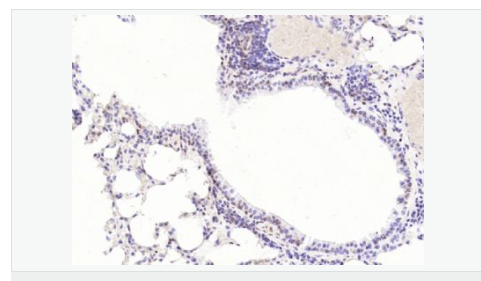

| 產(chǎn)品應(yīng)用 | WB=1:1000-2000 ELISA=1:1000-5000 IHC-P=1:100-500 IHC-F=1:100-500 Flow-Cyt=1ug/Test ICC=1:100-500 IF=1:100-500 (石蠟切片需做抗原修復(fù)) not yet tested in other applications. optimal dilutions/concentrations should be determined by the end user. |